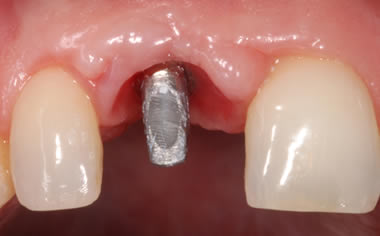

More front teeth replaced by dental implants

Case Three (4 images)